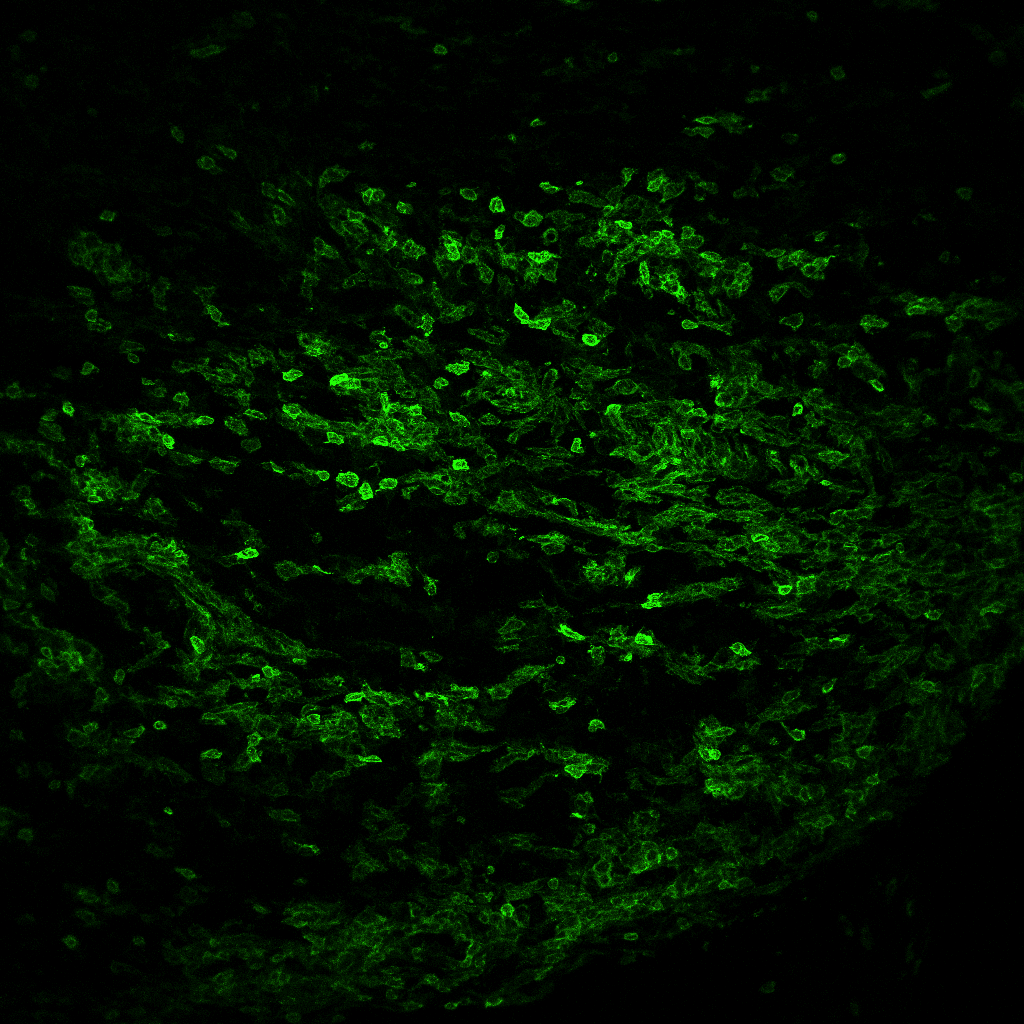

Striking Laboratory Data Images

Laboratory Data Gallery

Universe of the brain